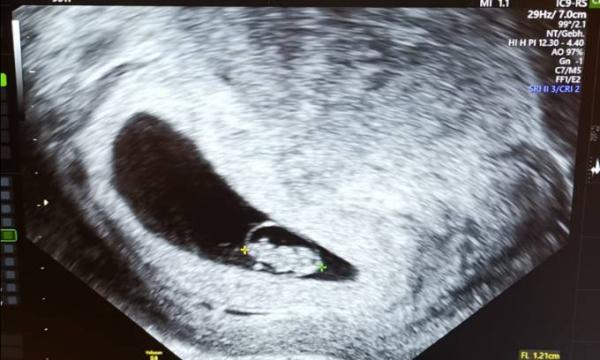

Huhu Soo nach den ganzen hin und her, dass es 2 waren, ist es dich nur eins. Die andere Fruchthöhle ist weg. Dem flips geht's super. Herzchen schlägt und ausgerechnet sind wir für den 11.7. In 2 Wochen geht's dann wieder zum Arzt.

Bild zu Flips geht's super - Forum für Juli - Mamis

Herzlichen Glückwunsch! Das hört sich toll an!!! Lese ich die Größe mit 1,2 cm richtig???

Ja es ist 1,2 cm groß

mein ET ist auch der 11.7 und mein US sieht auch so toll aus :))) Mein zwerg ist allerdings 1.6 groß :) Hab eine schöne Zeit :)